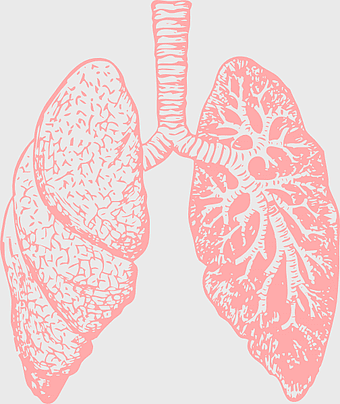

human lung anatomy, respiratory system illustration, heart and lungs diagram, bronchus structure, pulmonary function, thoracic cavity, medical imaging analysis -

3750x5000px

lung illustration, cartoon lung, organ diagram, animated lung, respiratory system, human anatomy, medical illustration -

747x606px

lungs illustration, respiratory system diagram, human lungs anatomy, pulmonary alveolus structure, bronchial tree visualization, trachea and bronchi, lung lobes detail -

1000x868px

lung organ, small lungs, respiratory system, pink trachea, human anatomy, medical illustration, pulmonary health -

1944x2122px

Respiratory system anatomy, human breathing process, pulmonary alveoli structure, respiratory therapist training, respiratory health education, lung function diagram, respiratory disease prevention -

1154x1321px

human lungs illustration, respiratory system anatomy, carina of trachea, blood vessel in lungs, pulmonary function, respiratory tract diagram, bronchial tree structure -

1347x1320px

Lung Respiratory system, trachea and bronchus, pink lungs illustration, breathing anatomy, pulmonary health, respiratory function, medical education visuals